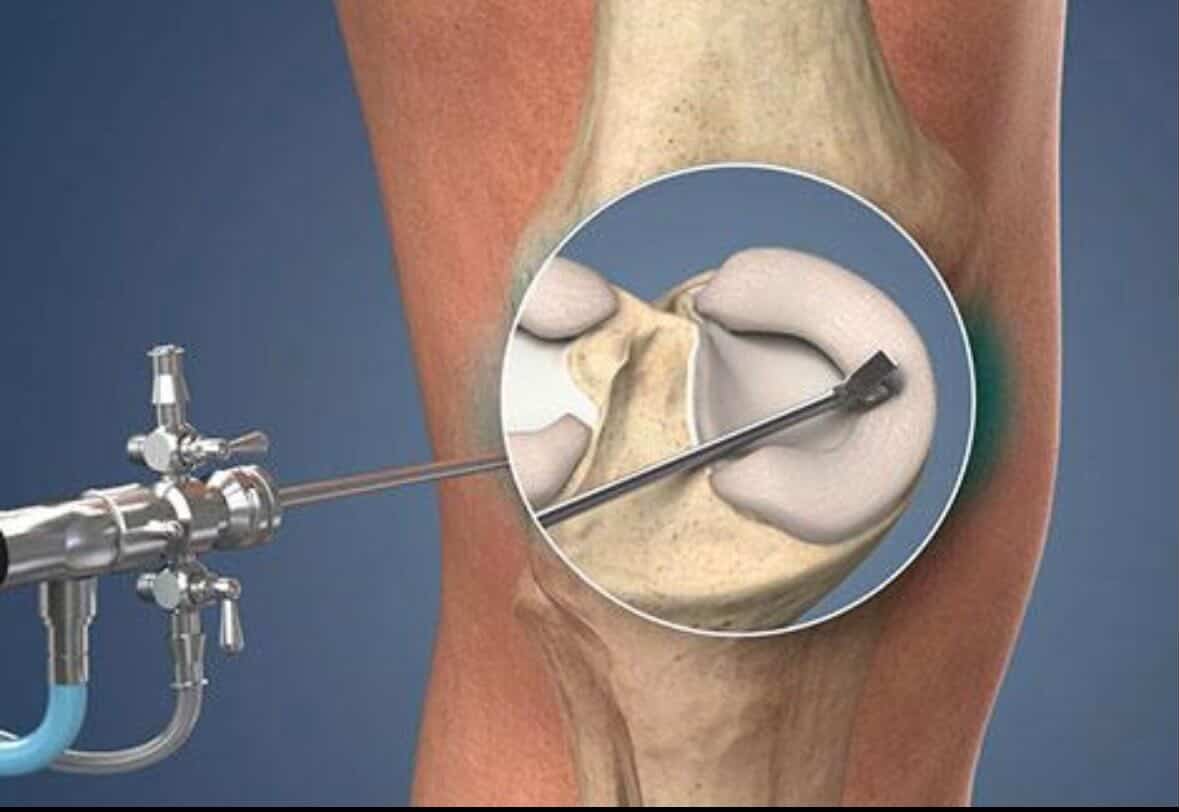

Advanced joint reconstruction using durable hip and knee replacement technology.

Reconstruction